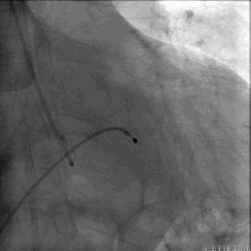

跨瓣DSA

瓣膜释放DSA